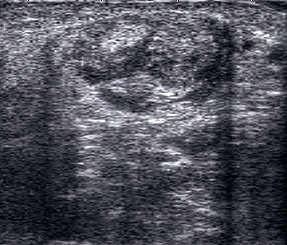

Peronealsehnenluxation

Peronealsehnenluxation. TS an der Fibulaspitze. Die Sehnen sind über die Fibula gerutscht.

Abbildung 45

Lagerung: Rückenlage, Innendrehung des Beins.

Schnittführung: TS und LS hinter dem Außenknöchel.

Referenzstrukturen: Fibulaspitze, Sehnen der Mm. peronaei.

Befunde: Halo-Phänomen. Bei der Luxation rutschen die Sehnen über den Außenknöchel nach lateral/ventral. Eine spontane Reposition unter Entspannung ist möglich. Im TS kann die Instabilität ggf. mittels Provokationstest durch Eversion gegen Widerstand sonographisch dynamisch dargestellt werden. Bei der Diagnostik der Peronealsehnen Instabilität oder Luxation ist die Sonographie durch die Möglichkeit der dynamischen Untersuchung dem MRT klar überlegen 4.